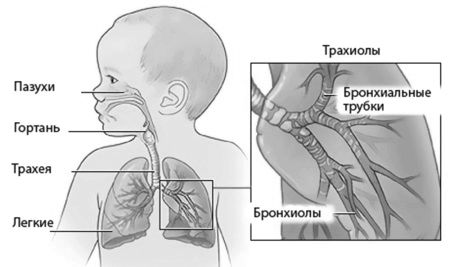

Запалення легенів у недоношених немовлят викликають бактерії, паразити, грибки або віруси. Їх потрапляння в дихальні шляхи малюка сприяють різні чинники, серед яких основними називають незрілість легенів, аспірацію під час пологів, інфекції в період внутрішньоутробного розвитку і ГРВІ.

Альвеоли в легких немовля, яке народилося раніше покладеного часу, в основному бувають недостатньо розправленими, а сурфактант може бути неякісним або незрілим. Крім того, у таких діток в легких відразу після пологів порушуються обмінні процеси і спостерігаються розлади кровообігу.

Далі до такої симптоматиці приєднуються розлади дихання. Малюк починає дихати часто, крила носа роздуваються, стають чутні хрипи, з'являються напади апное, періодичного дихання, кашель, спостерігаються западання проміжків між ребрами, частота скорочень серця збільшується, з рота може виділятися піниста слиз.